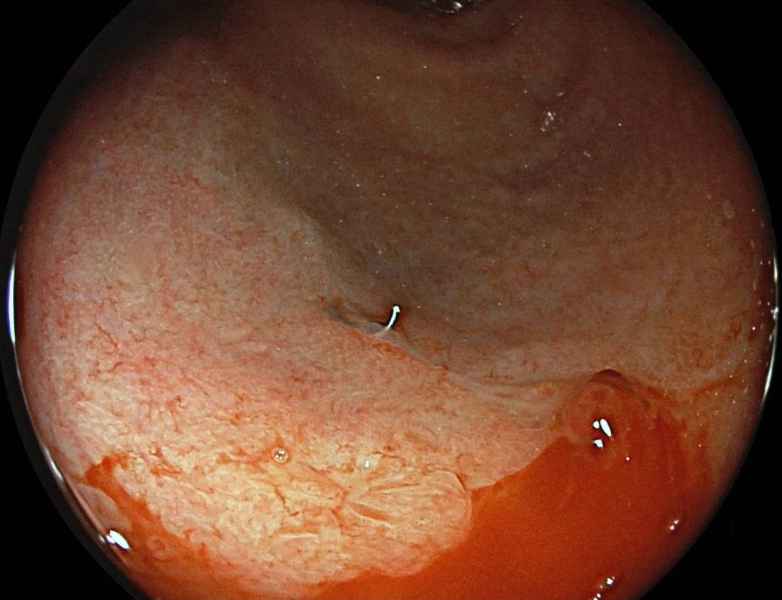

A plausible case of sloughing esophagitis